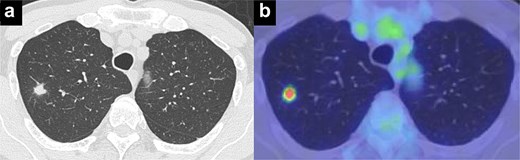

On POD 6, SE developed and spread to the chest, neck, and face. CT demonstrated remarkable mediastinal and SE with minimal lung collapse (Fig. 2; Video 2). Therefore, a chest tube was inserted, but minimal AL occurred from the chest tube, and the emphysema worsened. On POD 11, we performed thoracoscopic exploration and therapeutic intervention. Dense adhesion was confirmed between the staples on the interlobular plane and the dissected upper mediastinum. These were released, revealing the previous pleural tear. No other causative factors were observed. CT and operative findings suggested late-onset AL into the dissected mediastinum through dense adhesions. A leak test under positive pressure of up to 20 cmH2O revealed no AL from the pleural tear. The tear was sealed using a PGA sheet and fibrin glue, and 130 ml of autologous blood was injected into the pleural space to seal the dissected mediastinum and prevent air inflow (Video 3).

Image of postoperative mediastinal and SE with little lung collapse.